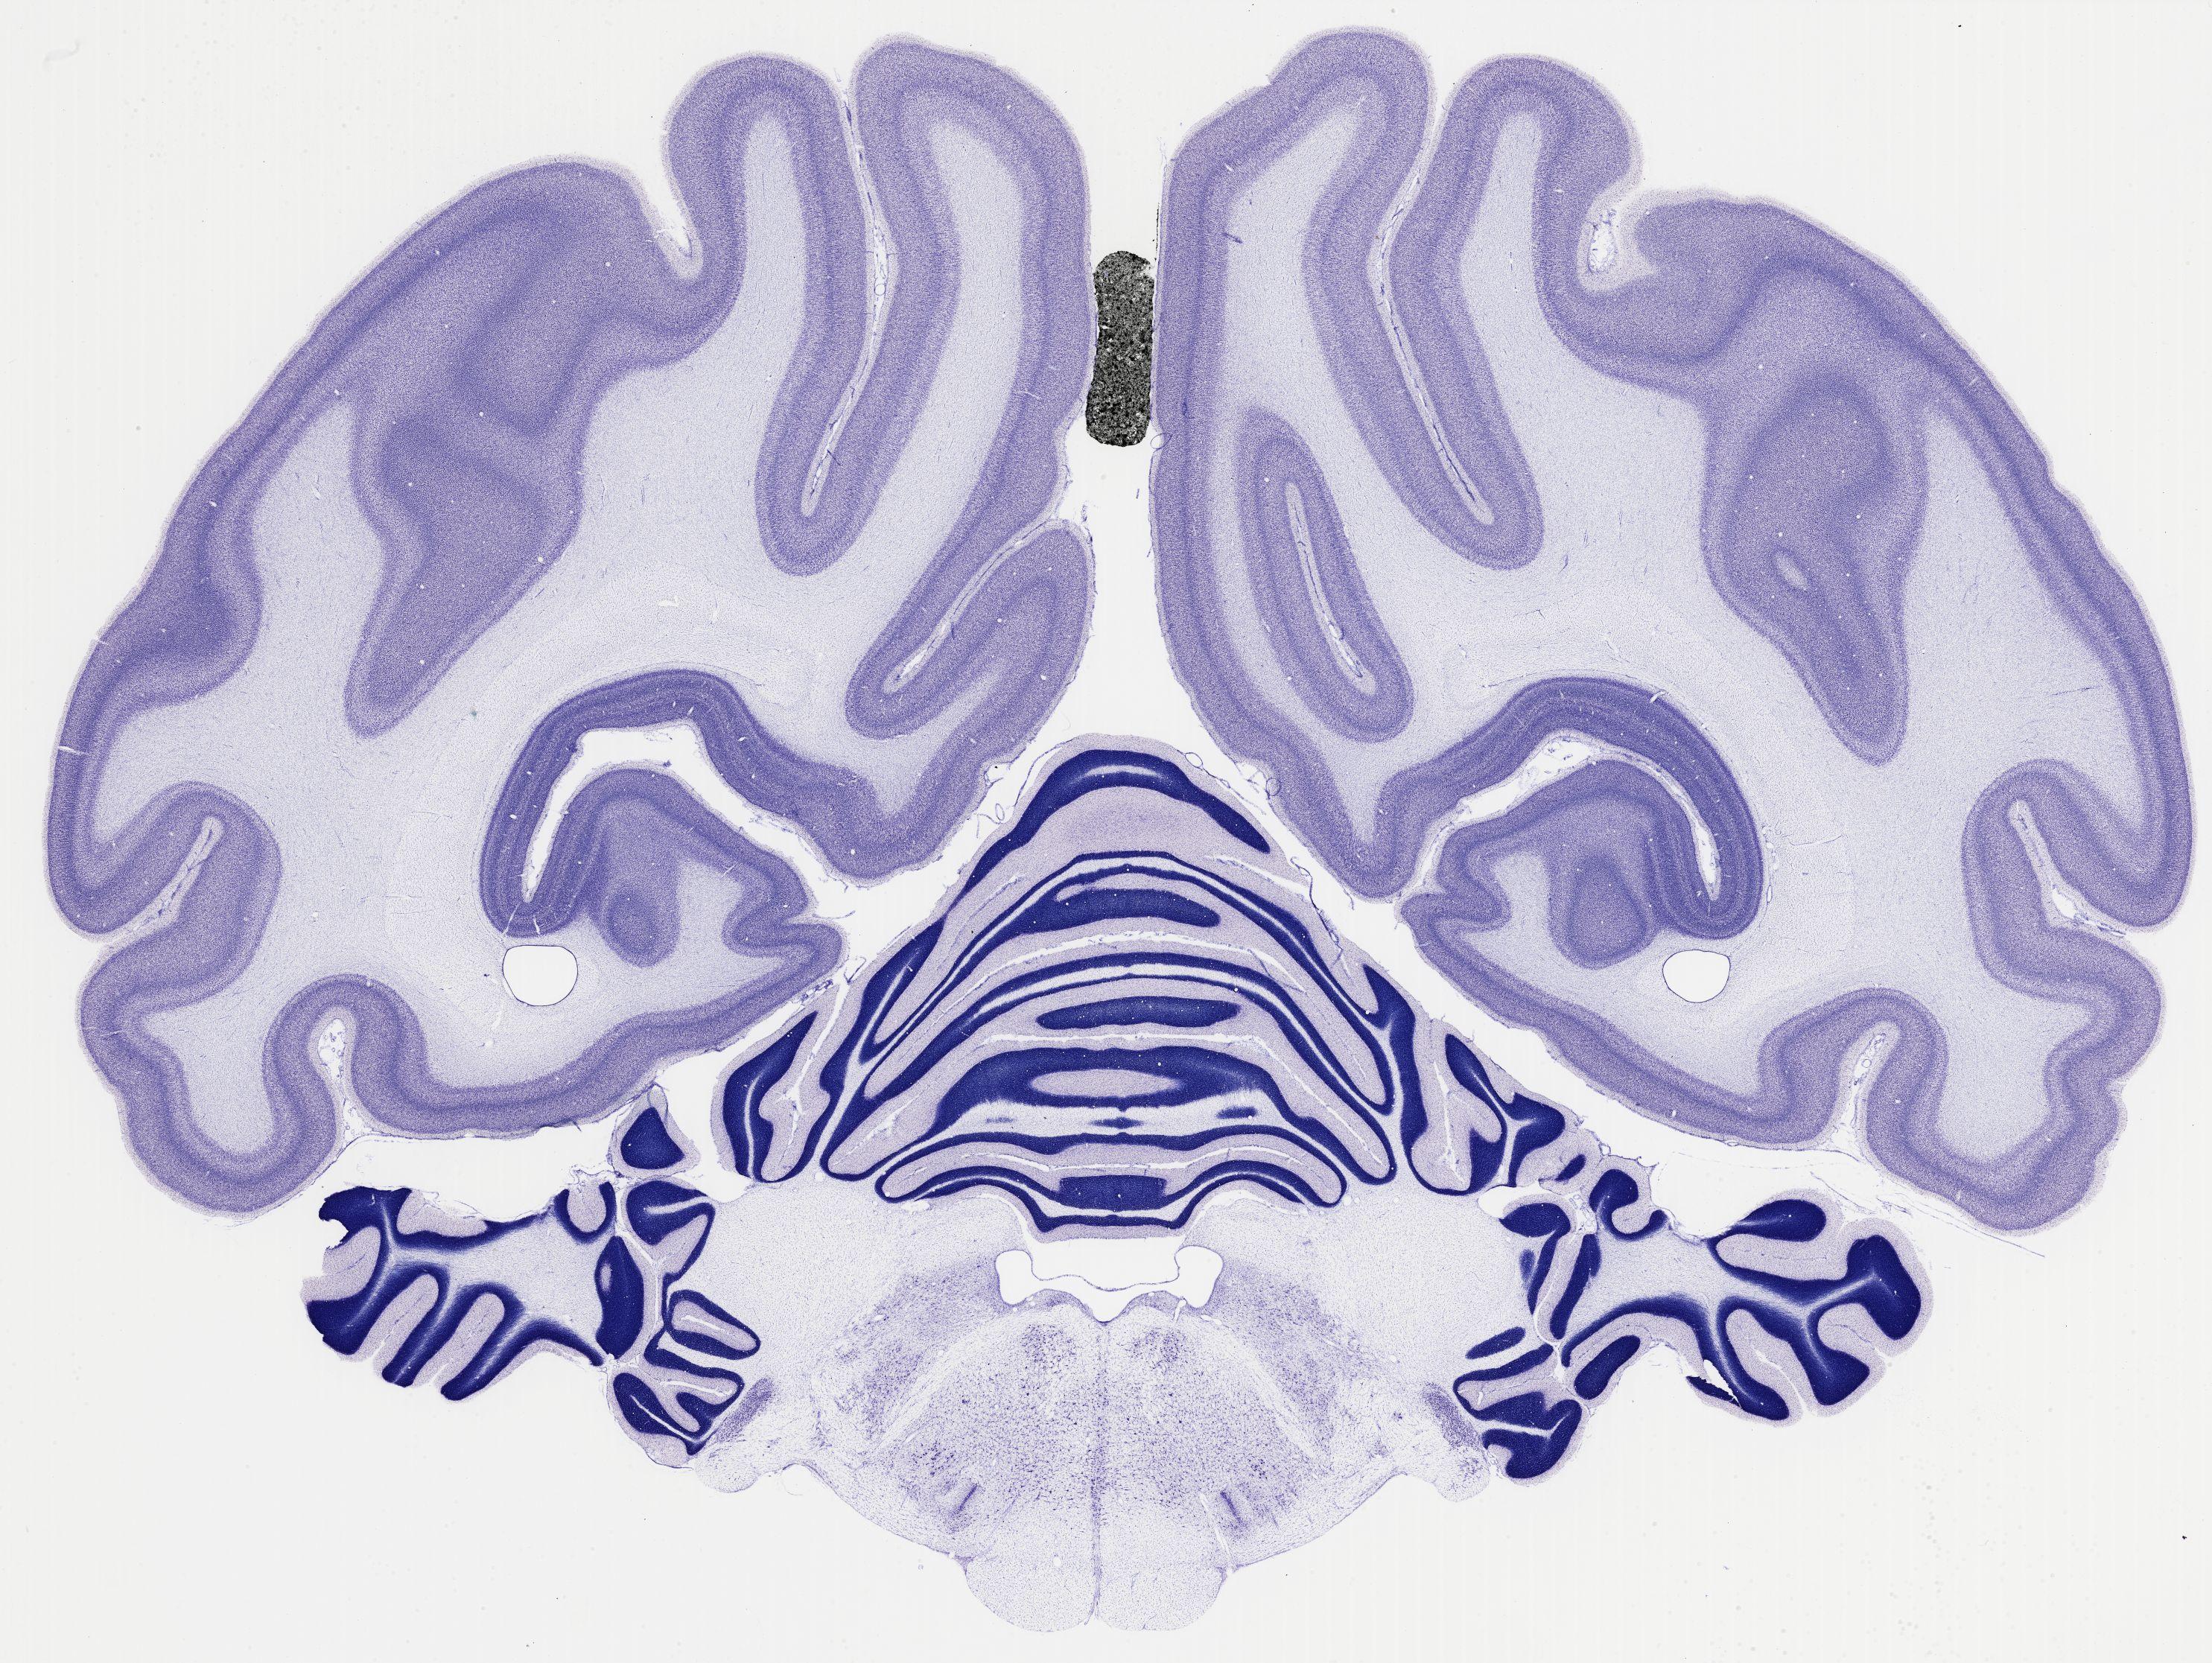

thumbnail

523